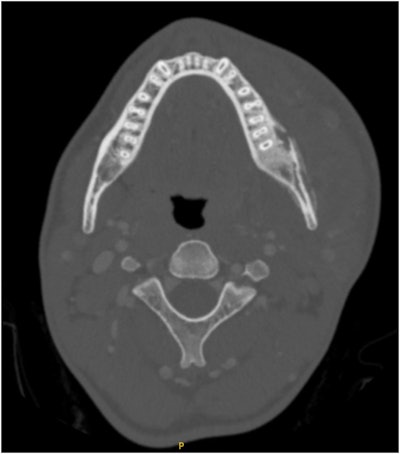

Axial CT scan demonstrating severe left hemimandible osteomyelitis with medullary and cortical osteolytic destruction and sclerosis with small abscesses on the buccal side of the mandible. Evidence of left masseter myositis and significant swelling of the masticator and left lingual space. Images courtesy of Podolsky et al. Licensed under CC BY-NC-ND 4.0.